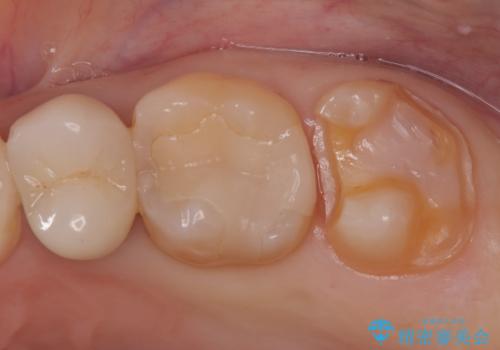

- 定期検診にて虫歯が見つかった患者様です。

金属のインレーの下と、歯と歯の間も虫歯だったため、つなげた形でセラミックインレーにて修復を行なっています。

e-max プレスインレーを用いることで、適合の良い治療ができます。